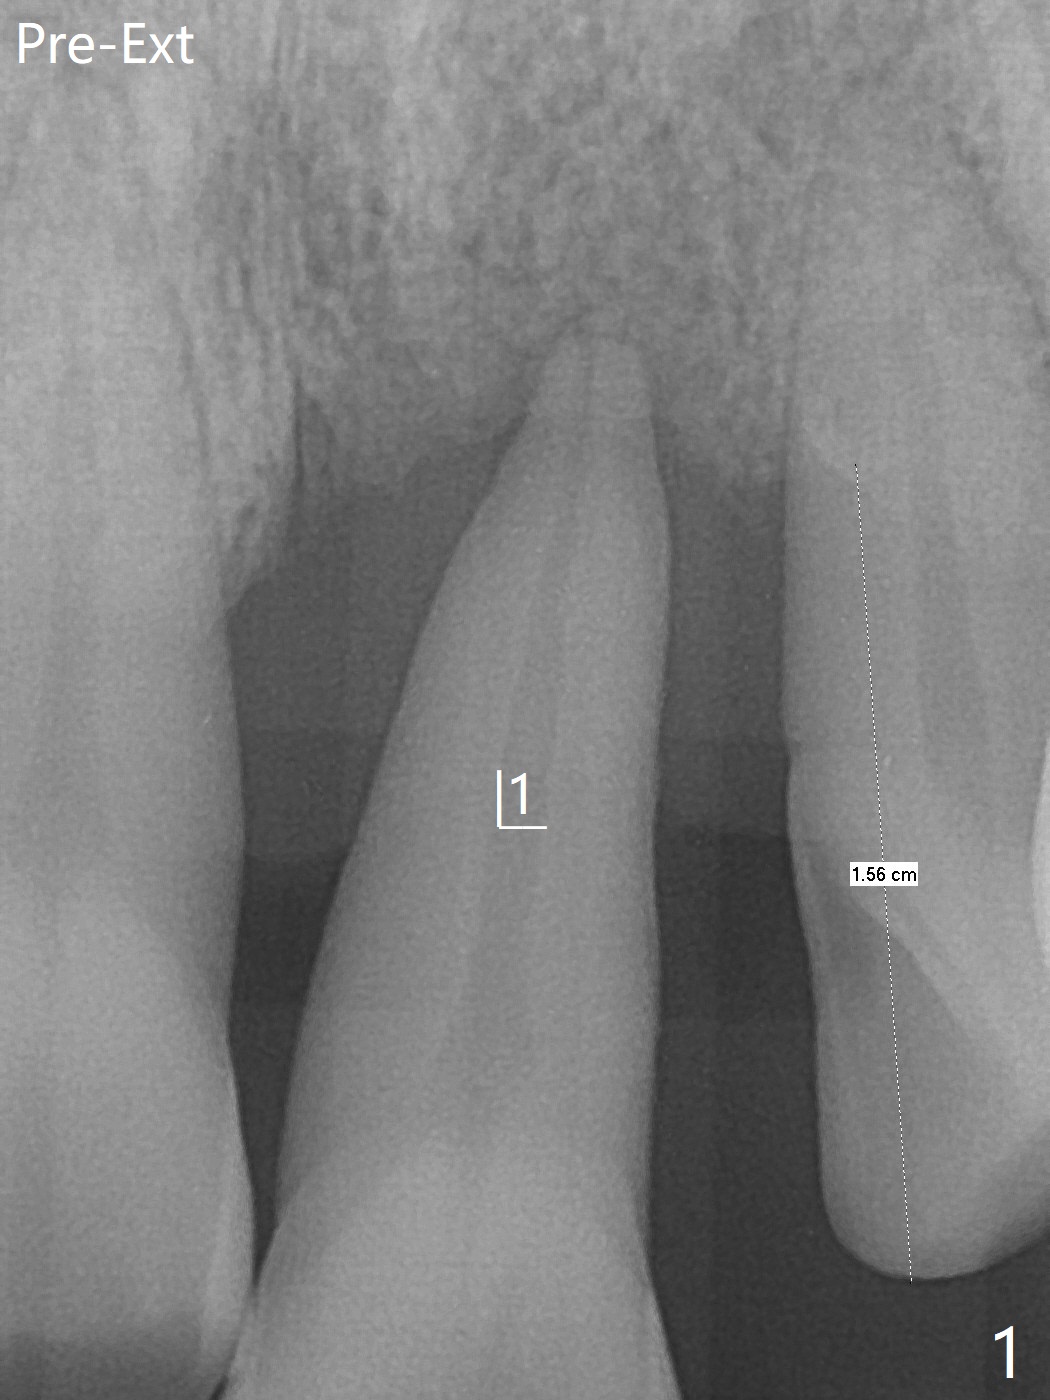

左上1(图一)拔除,植骨,使用带钛架不可吸收膜(图二)后十个月准备植牙(图三),在没有术中根尖片指导下(导板习惯),在牙槽嵴正中开始钻洞,第一个钻头最后一两个毫米觉得有突破感,但是颊侧舌侧没有穿孔,然后植入3.5x11.5毫米植体(图五,扭力>35 Ncm),术后射线表明植体接近切牙管(图四:*)。考虑到病人要离城,颊侧第一螺纹暴露(图六),舌侧骨板薄(图五),植骨,放置愈合基台(图七)。 术后十一天CT显示植体没有侵犯切牙管(图八:I);植体颊侧骨粉(箭头)似乎可以解释颊侧饱满(图九)。第二原因是减张缝合,胶原膜暴露(*),而下面骨粉没有暴露,以后伤口应该是二期愈合。